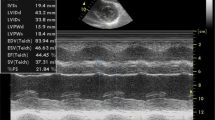

Most of the ventricular filling occurs in the first part of the diastole and is due to the ventricular suction. The latter is influenced by the stored energy generated by the previous systolic contraction. Therefore, diastolic function depends on the myocardial long-axis systolic function. In conclusion, diastolic impairment and longitudinal systolic dysfunction are the signs of cardiac amyloidosis in the earlier stage (Fig. 3).

Moderate increase of LV thickness (20 mm) (A), severe longitudinal dysfunction (S wave 0.03 m/s) on TDI (C), and severe diastolic dysfunction (E/E′23) (B). Note the absence of atrial function on PW Doppler. White arrows indicate a small pericardial effusion. (From Di Bella et al. Eur Heart J Cardiovasc Imaging. 2014 Dec;15(12):1307–15, by permission of Oxford University Press) [24••]